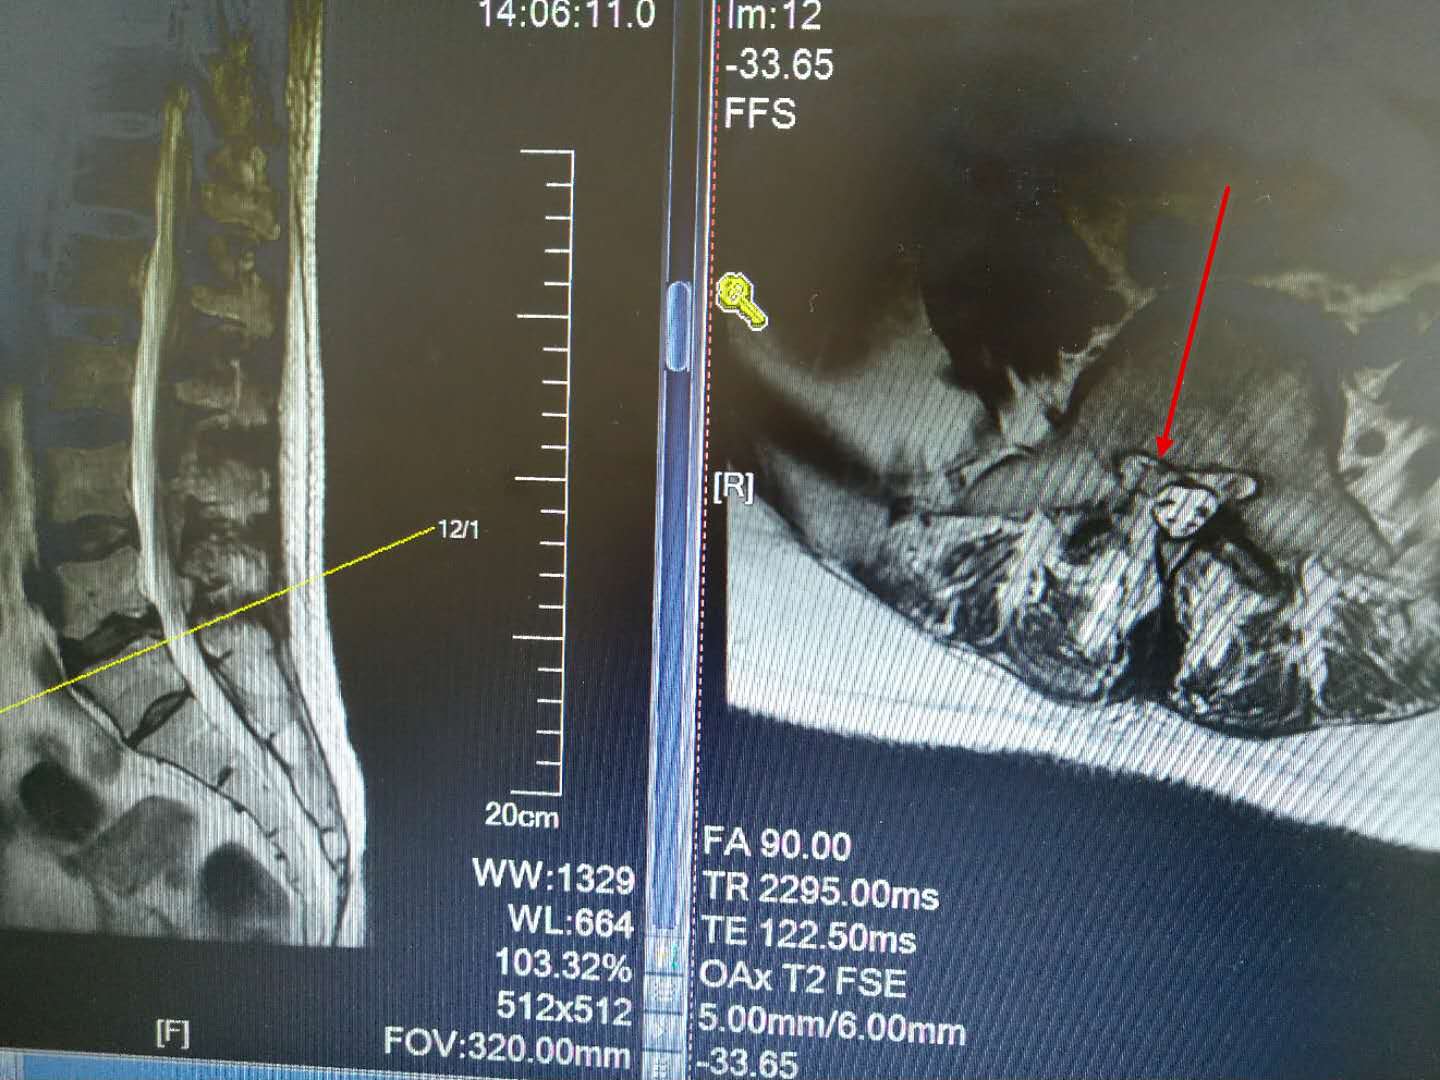

这是一例胸7-8间盘突出的患者,患者下肢无力越来越重,已经到了不能走路的地步,必须手术才能解决,可是胸椎手术风险比腰椎大的多,是真有可能瘫痪的,我们顶住压力,为了患者的健康着想,为他做了脊柱内镜下胸椎间盘摘除术。

手术很顺利,间盘摘除的很彻底,患者终于又可以站起来走路了。